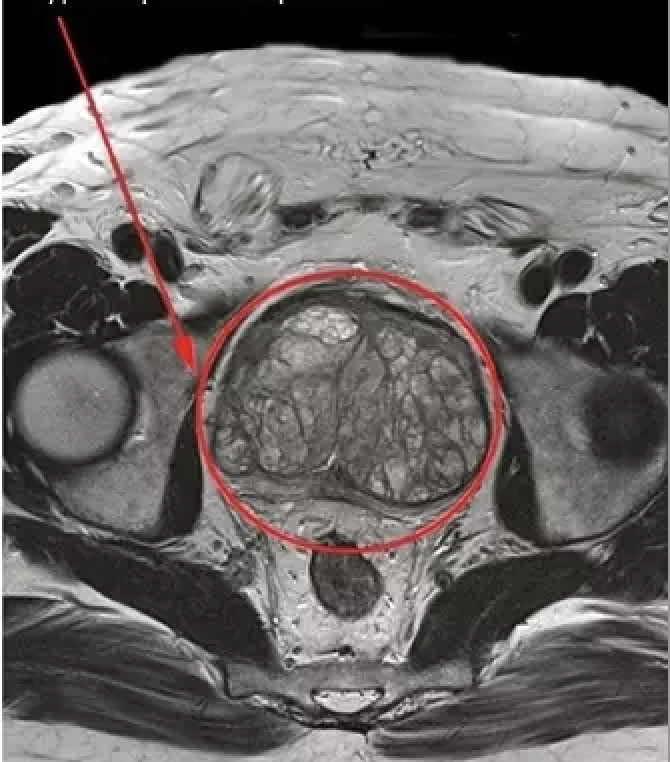

Moja prostata je bila velika kot

paradižnik! Ne dovolite, da bi to dosegla! Bala sem se iti spat, ker sem vedela, da bom trpela vso noč. Ravno ko sem hotela zaspati, se mi je spet mudilo na stranišče, šla sem na stranišče, vendar nisem mogla, bilo mi je tako vroče, da sem hotela jokati. Vedno znova sem zbujal ženo, da bi mi nekako pomagala, vendar ni bilo koristi. Posledica tega je bila, da vsa družina ni spala in je bila razdražena.